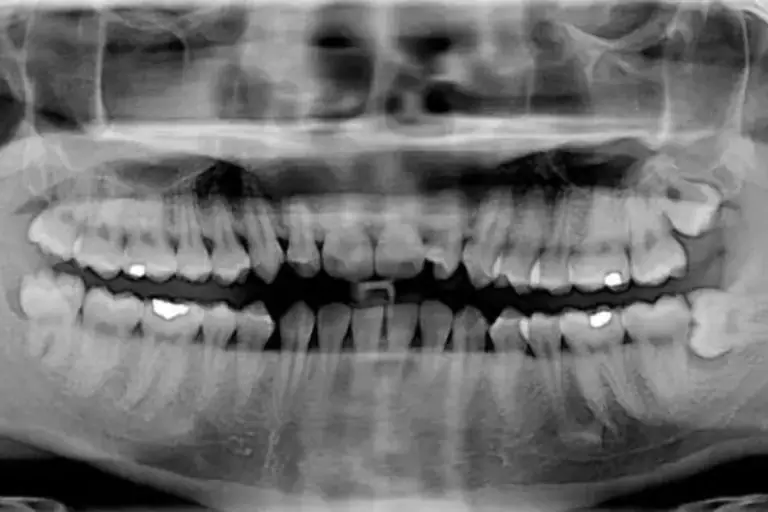

- ortopantomografia HD

- ortopantomografia CHILD